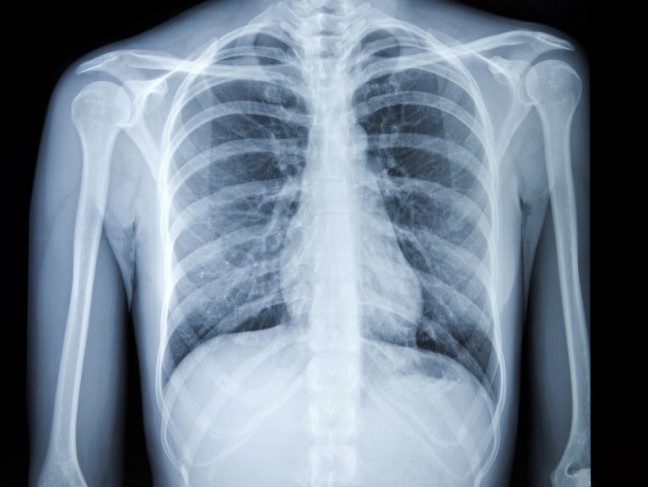

Radiografia – pune în evidență leziunile la nivelul plămânilor, dar nu este utilă în depistarea fracturilor costale, mai ales dacă osul prezintă doar mici crăpături.

Sursa foto: Pinterest @ Verywell